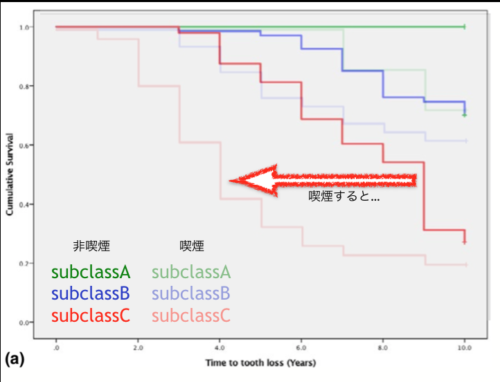

今回のテーマは、奥歯の歯周病で、特に分岐部病変と言われるものでした。

経過観察するにしても、どれくらいの生存率なのか、というところも勉強になりました。

そしてやっぱりタバコは歯の持ちを短くしてしまうということ。。